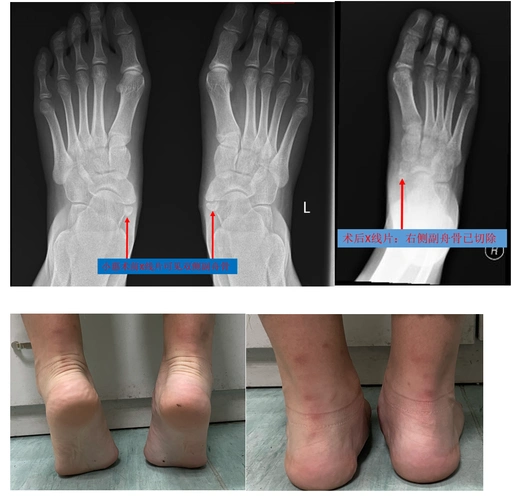

儿童少年时期脚痛的常见原因:副舟骨